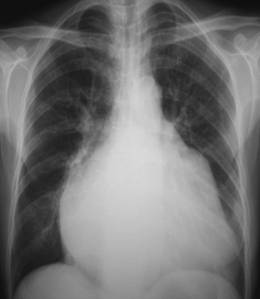

照片名称:高血压心脏病